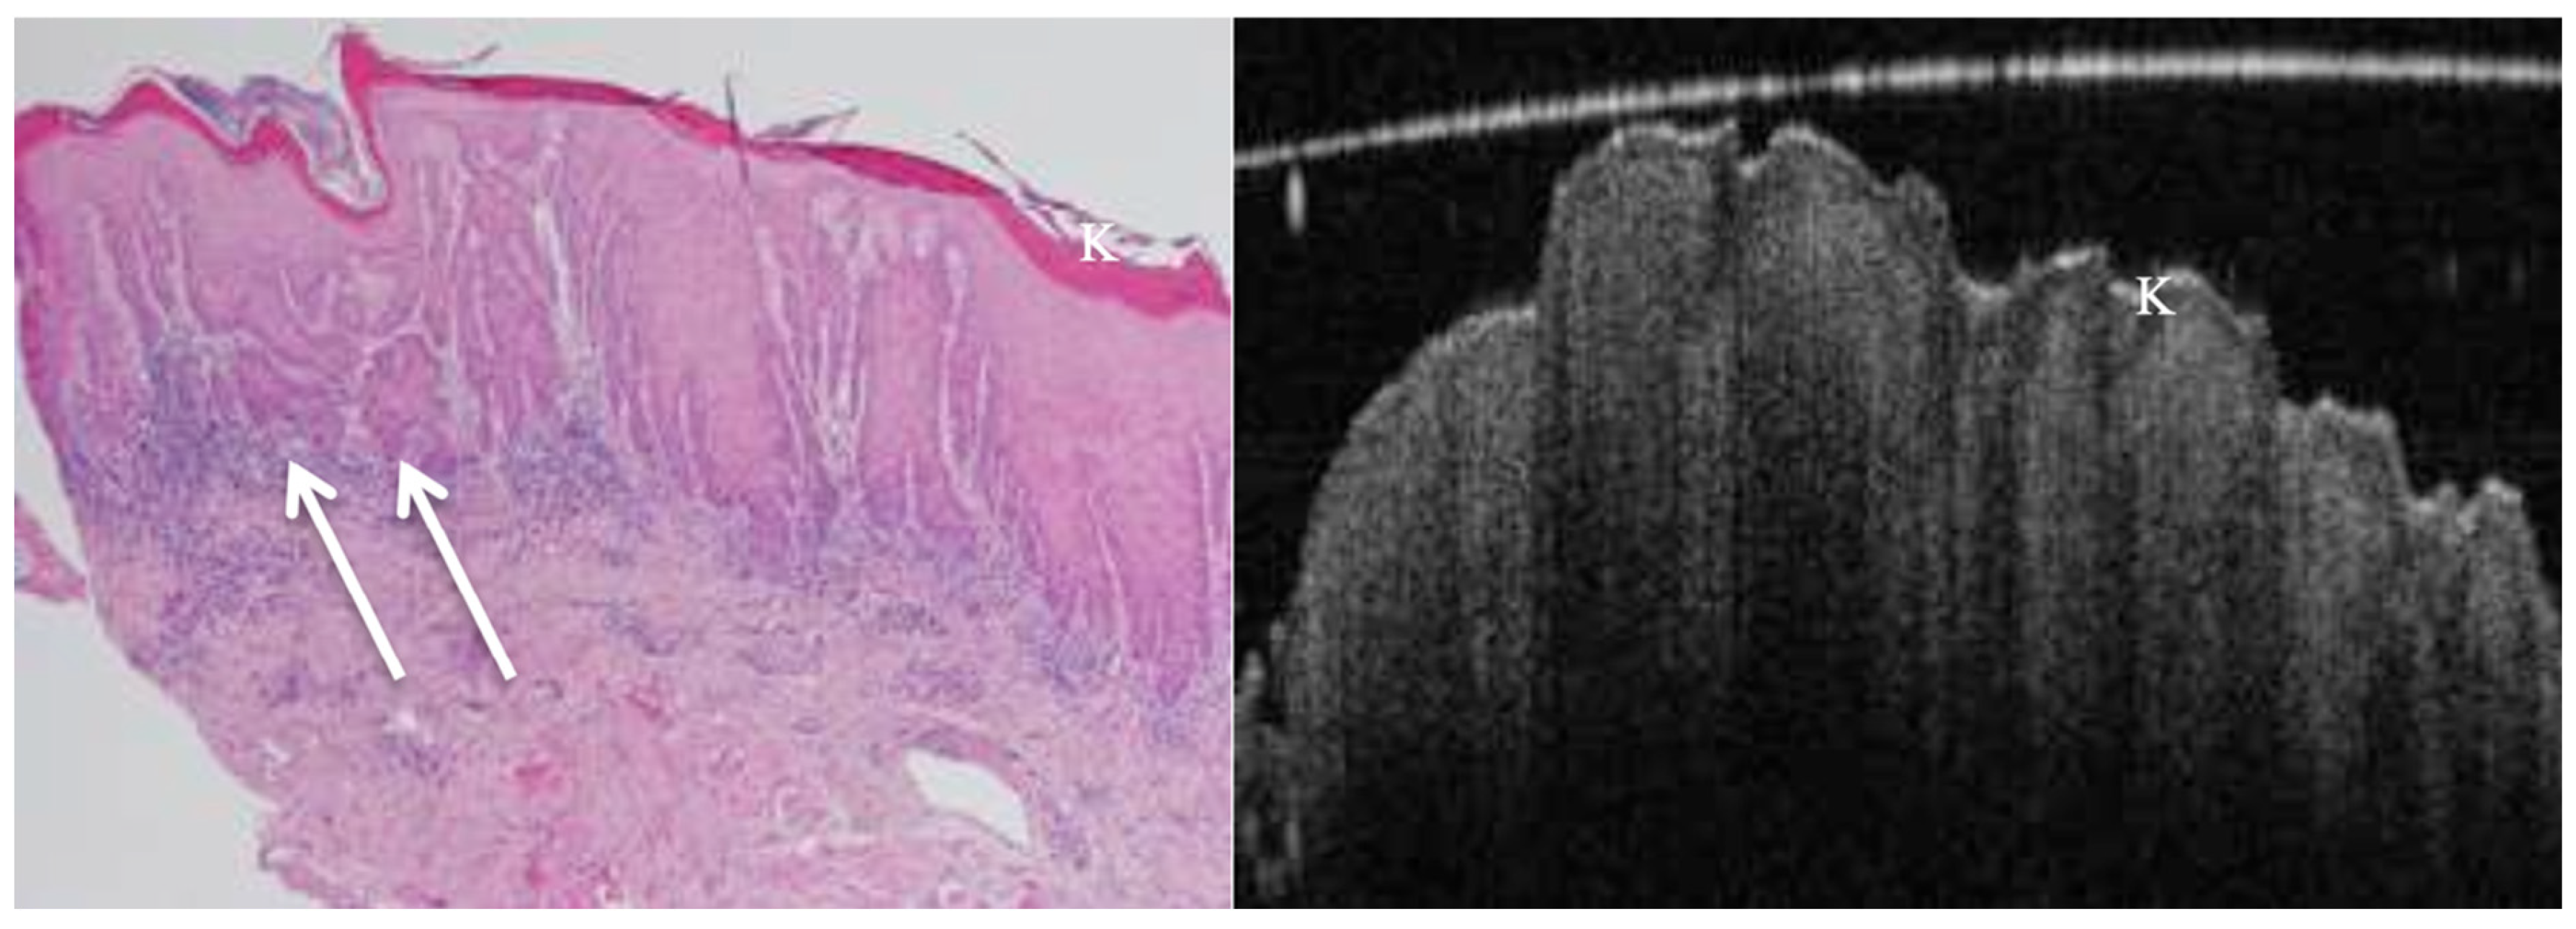

OCT performed well in discriminating dysplasia grades (Figure 1, Figure 2, Figure 3 and Figure 4). The AUC was 0.89 with an 88.0% sensitivity and 90.0% specificity for mild dysplasia. For moderate dysplasia, the highest accuracy was found: 85.0% sensitivity and 92.0% specificity yielded an AUC of 0.91. Severe dysplasia and CIS presented with lower values: the AUCs were 0.87 and 0.86, respectively (Table 4).

Figure 1. In vivo OCT and histopathology images of a white patch on the posterior lateral tongue reveal keratosis and mild to moderate epithelial dysplasia. K = keratosis.